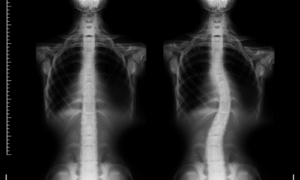

Skolioz onurğanın yana doğru əyilməsi və eyni zamanda burulması ilə xarakterizə olunan skelet sistemi pozğunluğudur. Normal halda onurğa arxadan baxıldıqda düz xətt şəklində olmalıdır. Skolioz zamanı isə onurğa sağa və ya sola doğru əyilir və bu əyilmə bədənin ümumi balansını pozur. Skolioz yalnız estetik problem deyil, eyni zamanda əzələ-skelet sisteminə ciddi təsir göstərən funksional bir vəziyyətdir. Əyrilik dərəcəsi artdıqca onurğaya düşən yük qeyri-bərabər paylanır və bu da bel ağrılarının yaranmasına səbəb olur.

Skolioz necə diaqnoz edilir?

Skoliozun diaqnozu adətən fiziki müayinə ilə başlayır. Həkim onurğanın vəziyyətini, duruşu və bədənin simmetriyasını qiymətləndirir. Lazım gəldikdə görüntüləmə üsullarından istifadə edilə bilər. Erkən diaqnoz skoliozun irəliləməsinin qarşısını almaq və bel ağrılarının nəzarət altına alınması üçün olduqca önəmlidir.